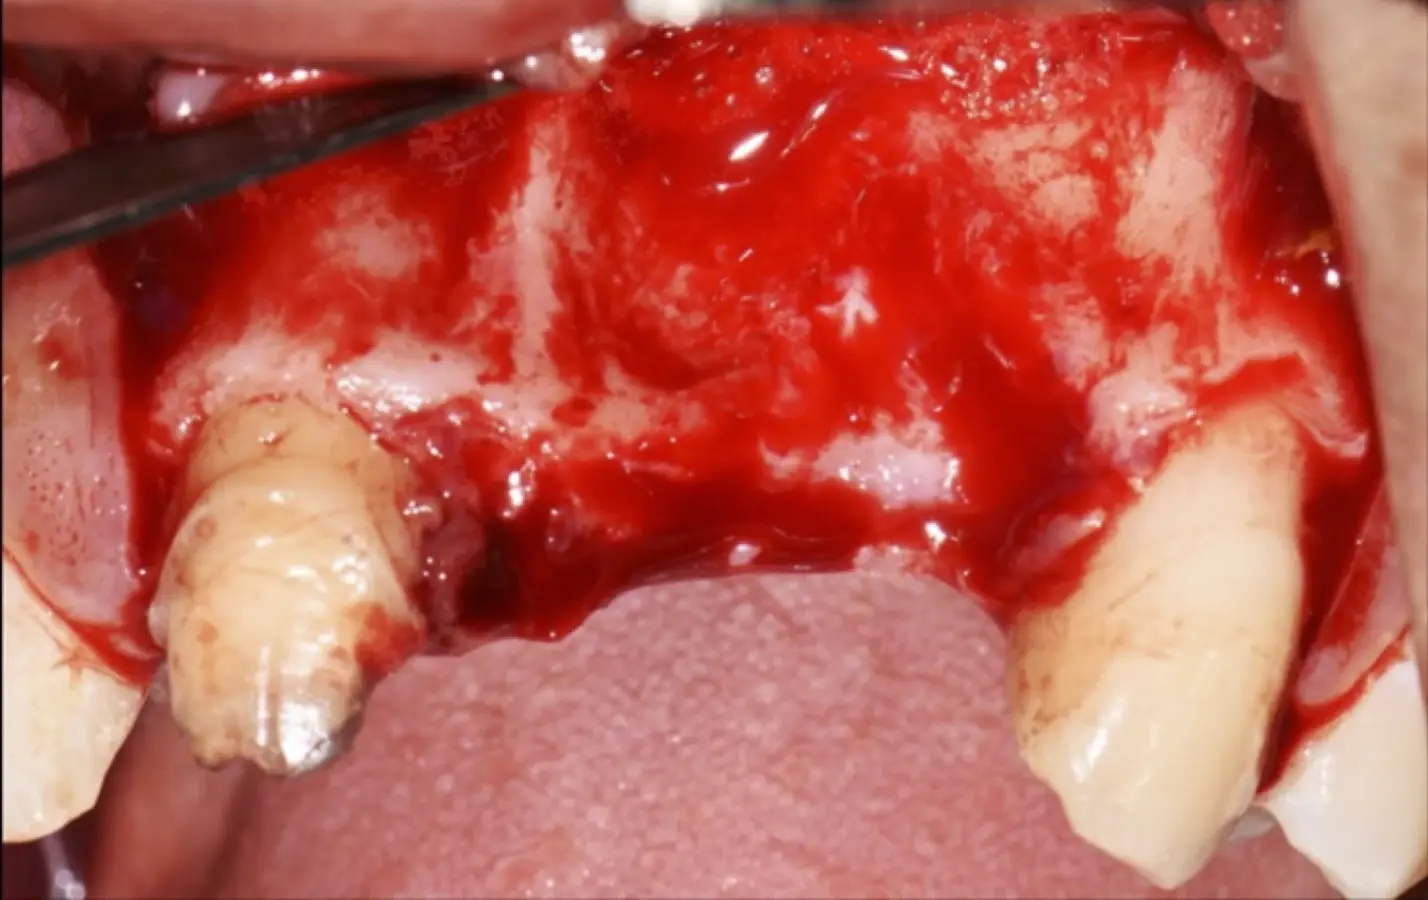

Figura 36. Defecto óseo y severa reabsorción ósea horizontal: vista clínica (a) y corte tomográfico (b).

Figura 44. Pasos para la colocación de la membrana de barrera (a - d).